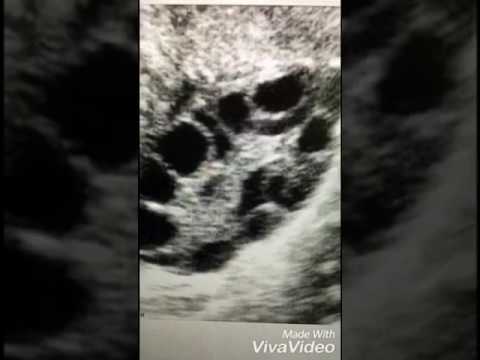

| د منى العواد/ تكيس المبايض/بث |

| تاريخ النشر 17/03/2021 |

| تكيس المبايض/د منى العواد |